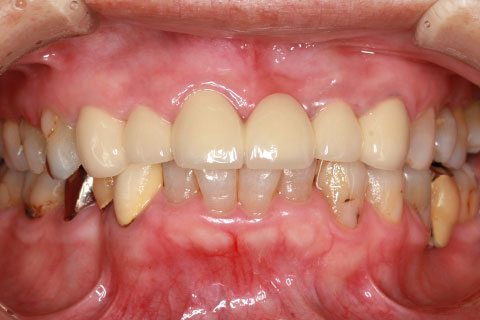

オールセラミックの症例2

- 年齢・性別

- 45歳男性

- 治療期間

- 2ヶ月

- 抜歯

- なし

- 治療費

- 70.4万円

- 備考

- 前歯8本の歯列不正によるセラミック治療

- 治療内容

- 歯質を削除し、セラミック冠をセメント合着

- 施術の副作用(リスク)

- 知覚過敏、歯髄炎、荷重負担